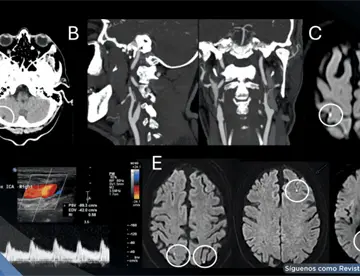

<content:encoded><![CDATA[<div><img src="https://blob.medicinaysaludpublica.com/images/2026/05/05/sacs-20--1096-06c07a35-focus-0-0-360-276.webp" alt="Estenosis subglótica oculta en adolescente asmática se revela durante intubación difícil en cirugía" title="Estenosis subglótica oculta en adolescente asmática se revela durante intubación difícil en cirugía"></div><p>La <strong><a href='https://medicinaysaludpublica.com/tags/paciente/25' target='_blank'>paciente</a></strong> femenina de 13 años con antecedente de ductus arterioso persistente corregido quirúrgicamente en el periodo neonatal, sin requerimiento posterior de intubación orotraqueal. Presentaba además diagnóstico de <strong><a href='https://medicinaysaludpublica.com/tags/asma/12927' target='_blank'>asma</a></strong> en manejo con beta-agonistas y esteroides inhalados, con persistencia de síntomas asociados al ejercicio, en seguimiento por neumología.</p>

<p>Consultó por hipoacusia y episodios recurrentes de otitis media durante la infancia. La valoración por otorrinolaringología evidenció una perforación timpánica subtotal derecha, por lo que se programó para timpanoplastia tipo I de forma ambulatoria. En la evaluación preanestésica fue clasificada como ASA II por su antecedente respiratorio, recomendándose continuar el tratamiento habitual.</p>

<p><strong data-start="1277" data-end="1313">Hallazgo inesperado en quirófano</strong></p>

<p>Durante la inducción anestésica se documentó dificultad para la intubación con tubo orotraqueal No. 6,0. La laringoscopia evidenció una estenosis concéntrica de la subglotis, lo que obligó a utilizar un tubo de menor calibre (No. 4,0). Ante este hallazgo y dada la disponibilidad de recursos, se realizó microendoscopia laríngea y broncoscopia en el mismo tiempo quirúrgico.</p>

<p>El estudio confirmó una estenosis subglótica concéntrica grado III según la clasificación de Cotton-Myer, con compromiso aproximado del 70% de la luz. Se efectuó dilatación laríngea e infiltración con mitomicina y triamcinolona, de acuerdo con el protocolo institucional, logrando mejoría del calibre de la vía aérea.</p>

<p><strong data-start="2011" data-end="2053">Claves diagnósticas en la espirometría</strong></p>

<p>La revisión de la espirometría prequirúrgica mostró parámetros globales dentro de la normalidad; sin embargo, destacaba un aplanamiento leve del pico espiratorio y un PEF reducido al 60%, con escasa respuesta a broncodilatadores.</p>

<p>El cálculo del índice de desproporción espiratoria (VEF1/PEFR × 100) fue de 50,4, valor sugestivo de obstrucción de la vía aérea superior, específicamente de estenosis laringotraqueal.</p>

<p>Este caso, según Gilberto&nbsp;Marrugo-Pardo et al., evidencia cómo una obstrucción de la vía aérea superior puede simular <strong>asma</strong>, especialmente cuando los síntomas predominantes son disnea y limitación al ejercicio. Aunque clásicamente el estridor orienta hacia compromiso laríngeo, su ausencia no excluye esta posibilidad, lo que puede conducir a diagnósticos erróneos.</p>

<p>En este caso, la aparente normalidad de la espirometría pudo explicarse por el esfuerzo muscular de la <strong>paciente</strong>, enmascarando la obstrucción. No obstante, la alteración aislada del PEF y el índice de desproporción espiratoria ofrecían pistas diagnósticas relevantes.</p>